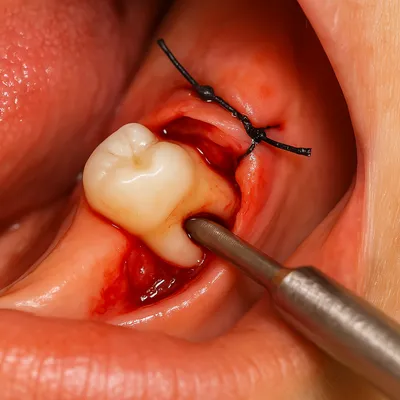

نمای واقعی از جراحی داخل دهان با بخیه لثه و خارج کردن دندان نهفته

مقایسه جراحی ساده دندان عقل با جراحی نهفته

کشیدن دندان عقل رویشی ساده معمولاً فرآیندی کوتاه و کمهزینه است، زیرا دندان کاملاً از لثه بیرون آمده و جراح تنها با بیحسی موضعی میتواند آن را خارج کند. در چنین شرایطی، بیمار نیازی به برش لثه، بخیه یا برداشت استخوان ندارد و تعرفه پایینتر محاسبه میشود.

اما در مواردی که دندان بهصورت نیمهنهفته یا کاملاً نهفته در فک قرار دارد، جراحی پیچیدهتر میشود. نیاز به برش لثه، دسترسی به دندان در عمق استخوان، استفاده از تجهیزات پیشرفته و گاهی بیهوشی یا سدیشن باعث میشود هزینه جراحی دندان عقل نهفته بهمراتب بیشتر از کشیدن ساده باشد.

همین تفاوت در سختی کار است که موجب اختلاف قیمت بین کشیدن معمولی و هزینه جراحی دندان عقل نهفته میشود.

به بیان ساده، هرچه دسترسی به دندان دشوارتر و میزان مداخله جراحی بیشتر باشد، تعرفه بالاتر خواهد بود؛ بنابراین معاینه دقیق و تصویربرداری پیش از عمل برای برآورد درست هزینه ضروری است.